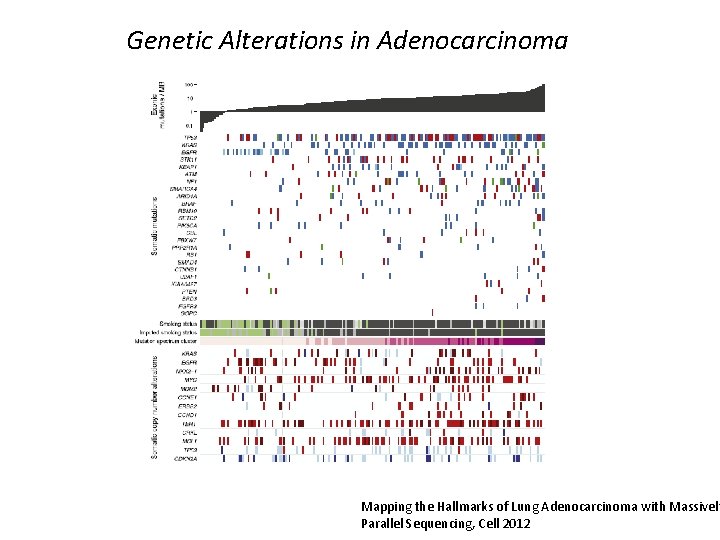

Mutational Profiling in Lung Adenocarcinoma AKT 1% ROS 1 1. 5% BRAF 2% HER 2 2% CTNNB 1 2% ALK 3% PIK 3 CA 4% NRAS 1% RET 1% IDH 1 <1% TP 53 5% No Mutation ~40% EGFR 15% KRAS 23%

Genetic Alterations in Adenocarcinoma Mapping the Hallmarks of Lung Adenocarcinoma with Massively Parallel Sequencing, Cell 2012